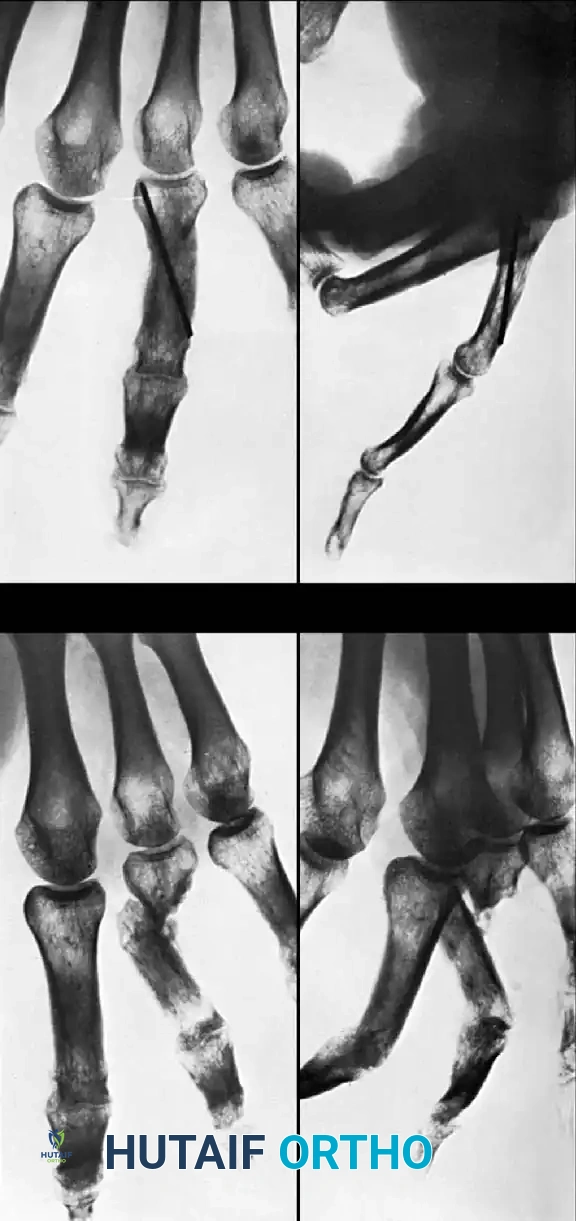

Fig. 64-74 A, Malunited phalangeal fracture with rotational deformity. B, After treatment by osteotomy through proximal end of bone and fixation with two Kirschner wires. Healing usually is more rapid after osteotomy at this level than after one at old fracture.